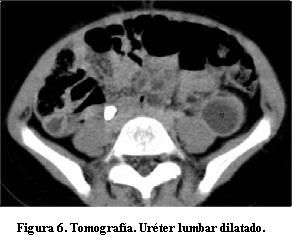

Marcada uréterohidronefrosis izquierda; el parénquima del riñón izquierdo presenta escaso espesor y las cavidades pielocaliciales dilatadas (figuras 3, 4 y 5), con uréter tortuoso en todos sus sectores (figura 6), el cual se afina abruptamente en el sector prevesical inmediato. En el uréter no se observa litiasis de alta densidad, ni compresiones extrínsecas. Riñón derecho sin alteraciones. La vejiga no presenta alteraciones en la pared ni en el contenido. No hay adenomegalias en los territorios estudiados. Hígado, bazo y páncreas sin particularidades. No hay ascitis.